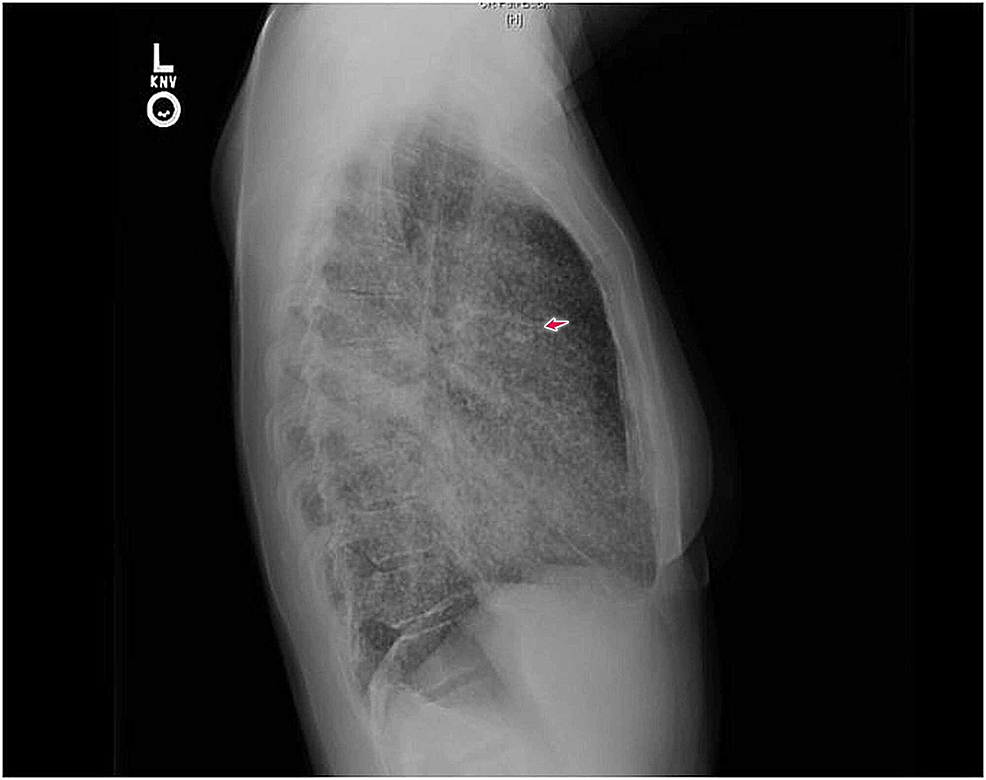

From www.cureus.com

Cureus Adenocarcinoma of the Lung Presenting with Intrapulmonary Miliary Chest X-Ray Differential Diagnosis In selected cases the distribution of. Miliary nodules can be the manifestation of multiple diseases and the differential diagnosis is broad once. The differential diagnosis of miliary pattern on chest radiography includes miliary tuberculosis (tb), histoplasmosis, sarcoidosis, pneumoconiosis, bronchoalveolar carcinoma,. The differential diagnosis of miliary pattern on chest radiography includes miliary tuberculosis (tb), histoplasmosis, sarcoidosis,. Histological confirmation of the diagnosis. Miliary Chest X-Ray Differential Diagnosis.